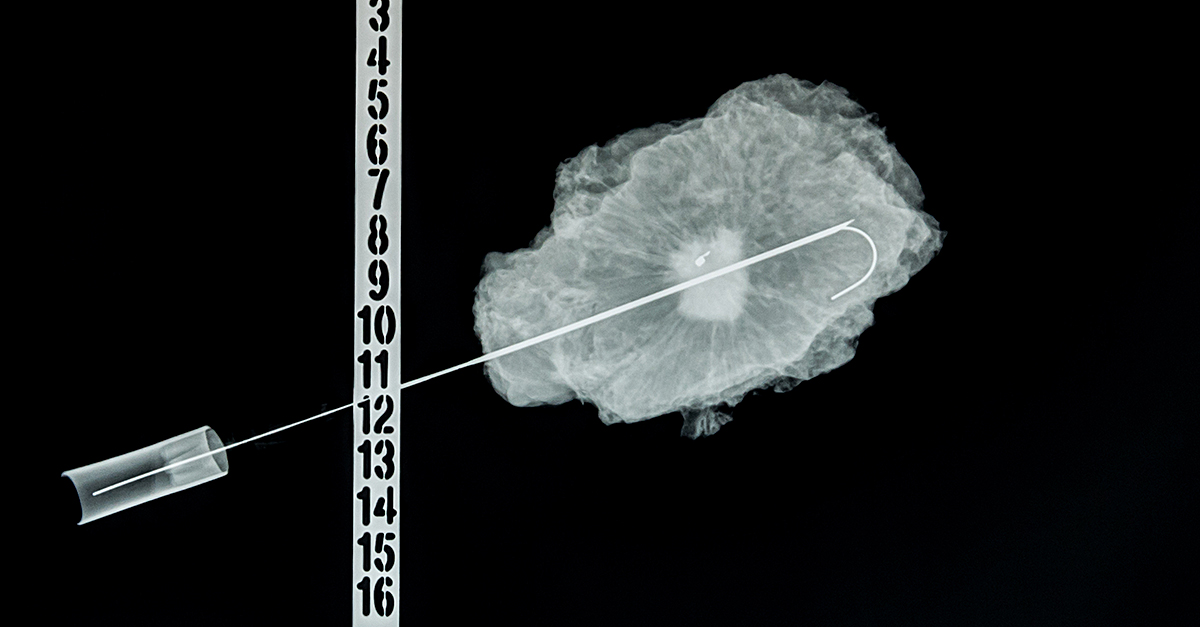

Biopsy steps may differ depending on the type of procedure. A transrectal biopsy involves going through the rectum, while a transperineal biopsy is taken through the perineum, the area between the anus and the scrotum. The latter is usually guided by a computerized tomography (CT) scan or an MRI.

Broadly speaking, more traditional biopsies will use a probe and attached needles to take tissue samples.

One of the newer diagnostic steps in the field is conducting an MRI. Using this technology, doctors can get a more detailed picture of the prostate and determine what level of care each patient needs. An MRI can help a medical team see exactly where a lesion is located and, if needed, collect tissue samples more precisely during a biopsy.